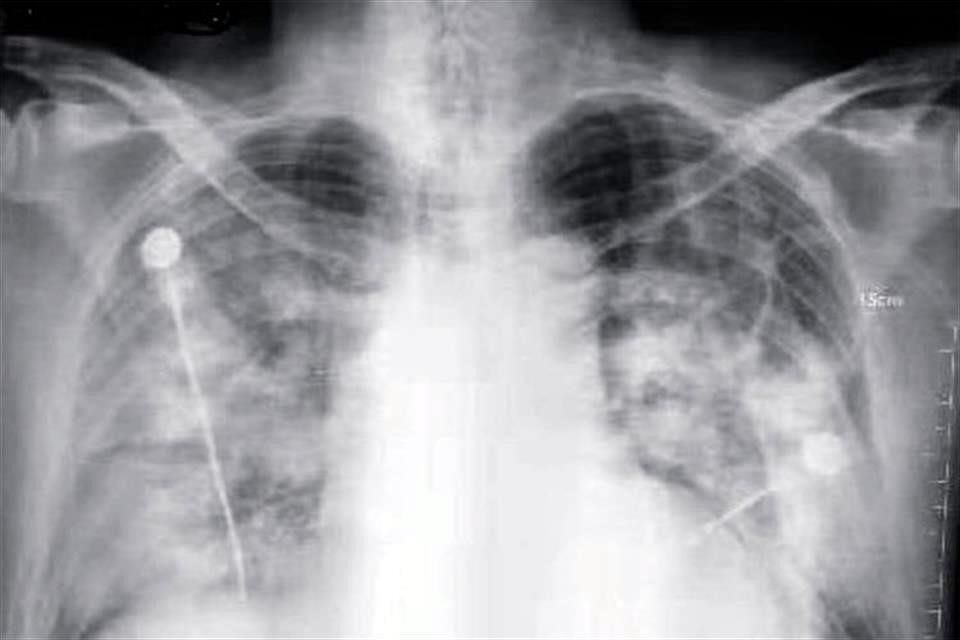

En Estados Unidos se registraron 200 casos de una misteriosa fibrosis pulmonar que podría obedecer al COVID-19.

El virólogo taiwanés recordó además que recientemente en Estados Unidos se han registrado más de 200 casos de una extraña «fibrosis pulmonar», que han causado la muerte debido a la incapacidad de los pacientes para respirar, y cuyas afecciones y síntomas no han podido explicarse.

El científico escribió artículos informando a las autoridades de salud de ese país que consideraran seriamente que esas muertes fueron resultado del coronavirus, aunque fueran atribuidas a los cigarrillos electrónicos, sin ahondar más en el tema.